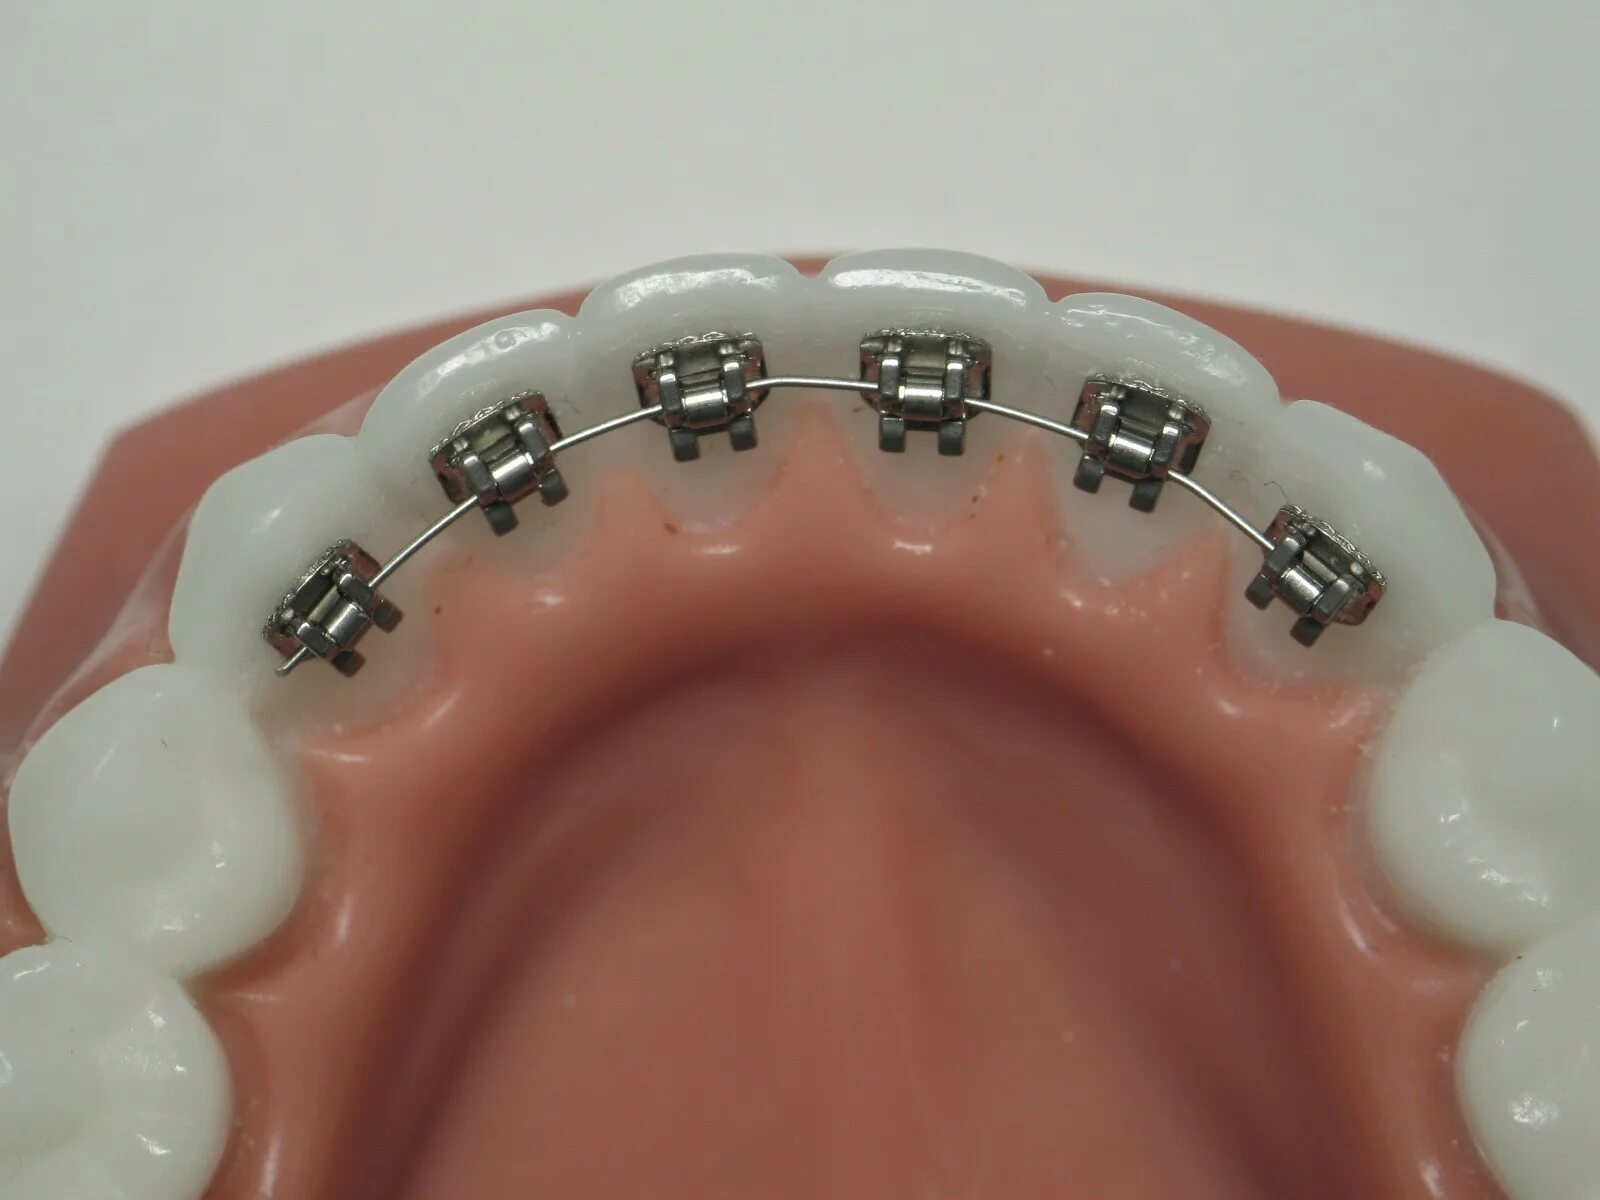

Поставить 4 зуба